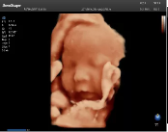

容積探頭是在二維圖像的基礎(chǔ)上,將連續(xù)采集的空間分布位置,經(jīng)過計算機(jī)重建算法,從而獲得完整的空間形態(tài)。

適用于:胎兒面部、脊柱和肢體等。

優(yōu)勢特點:快速獲取、掃查連續(xù)均勻、解剖結(jié)構(gòu)顯示為容積數(shù)據(jù)、準(zhǔn)確進(jìn)行容積測量。